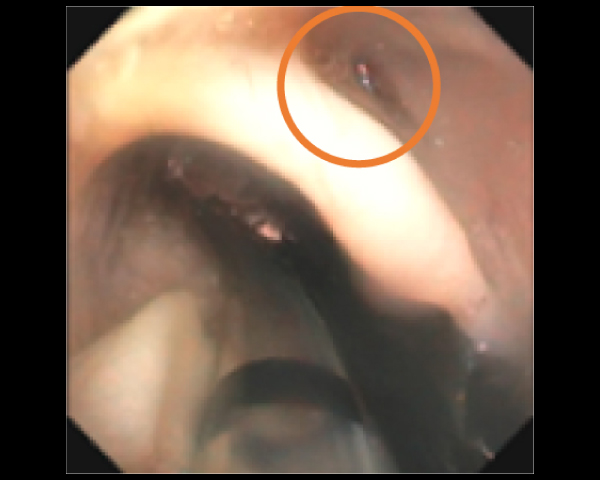

内視鏡で狭窄部位を確認

拡張後の鼻咽頭部